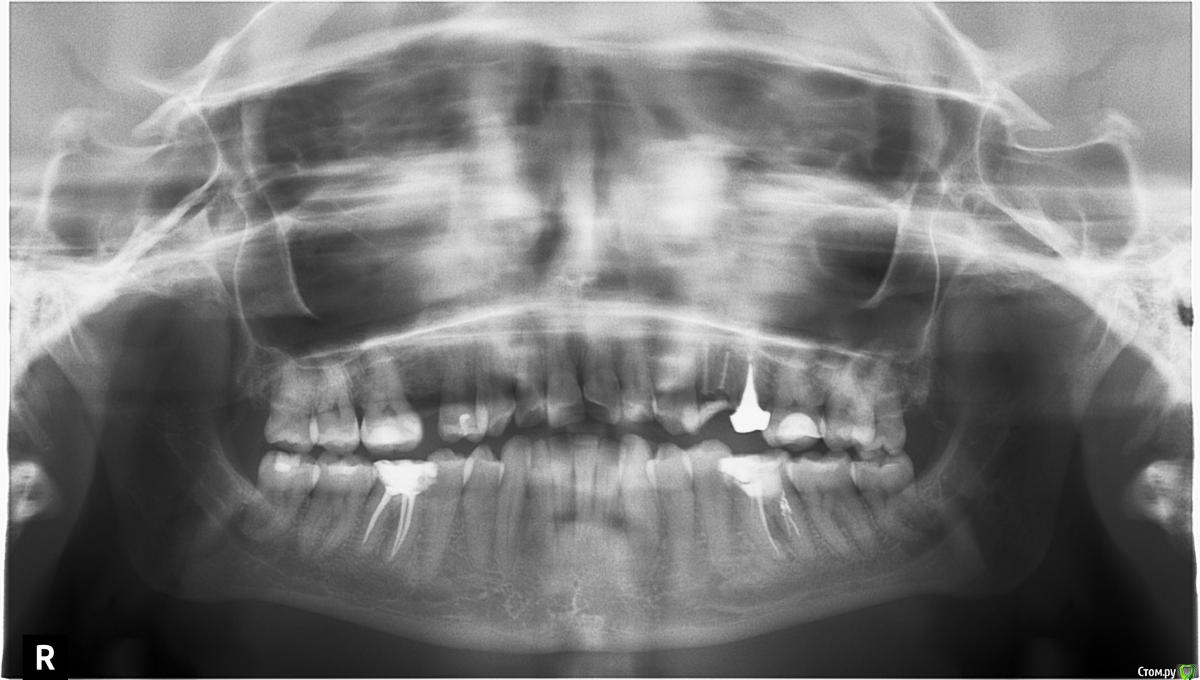

Аннана Опубликовано 22 января, 2018 Поделиться Опубликовано 22 января, 2018 Здравствуйте! Пожалуйста, подскажите, что делать с 46 зубом? На нем киста, ее пытались вылечить, зуб не болит не шатается. Большинство врачей склоняются к тому, чтобы ставить штифт и коронку, но некоторые предлагают удалить и ставить имплантат, т к плохой канал. Ссылка на комментарий

DmitrySH Опубликовано 22 января, 2018 Поделиться Опубликовано 22 января, 2018 46 - перелечить и покрыть коронкой. При адекватном исполнении будет еще долго вам служить.36 - неоднозначно. По данному снимку я бы не делал прогнозов. Ссылка на комментарий

Петр Бриньковский Опубликовано 24 января, 2018 Поделиться Опубликовано 24 января, 2018 Здравствуйте! Пожалуйста, подскажите, что делать с 46 зубом? На нем киста, ее пытались вылечить, зуб не болит не шатается. Большинство врачей склоняются к тому, чтобы ставить штифт и коронку, но некоторые предлагают удалить и ставить имплантат, т к плохой канал.Здравствуйте! Даже при перелечивании корневых каналов на 100 % гарантий Вам никто не даст.., дальше зуб необходимо восстанавливать штифтово-культиевой вкладкой и покрывать коронкой. Необходимо конечно посмотреть КТ, но даже по данному снимку видно, что коронковая часть зуба достаточно разрушена и практически весь-зуб это большая пломба, система корневых каналов также уже расширена до нельзя(перелечивали), под вкладку или штифты придется еще расширять , просто вся эта структура может просто сломаться, достаточно ненадежна и Вы потеряете и деньги и время, в данном случае более прогнозируемо будет удаление этого зуба и установка имплантанта ! Ссылка на комментарий